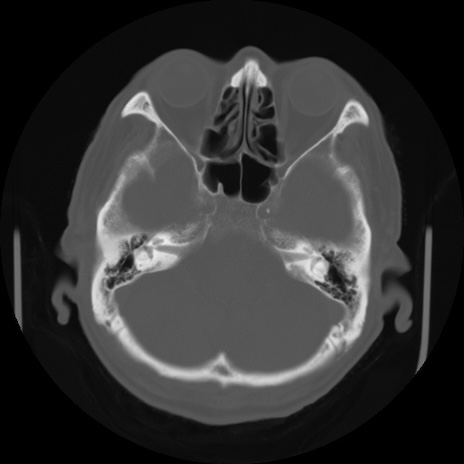

【頭部】症例5 CT(横断像)

【症例】80歳代 男性

【主訴】頭部打撲

【現病歴】外出先で椅子から立ち上がる際に、つまづいて後方へ転倒し受傷。転倒時に意識はあった。

【身体所見】BP 217/71、HR 96、JCS1-1、 難聴あり、顔色良好、右後頭部に擦過創あり。神経学的異常なし。

症例5の画像所見と診断は?